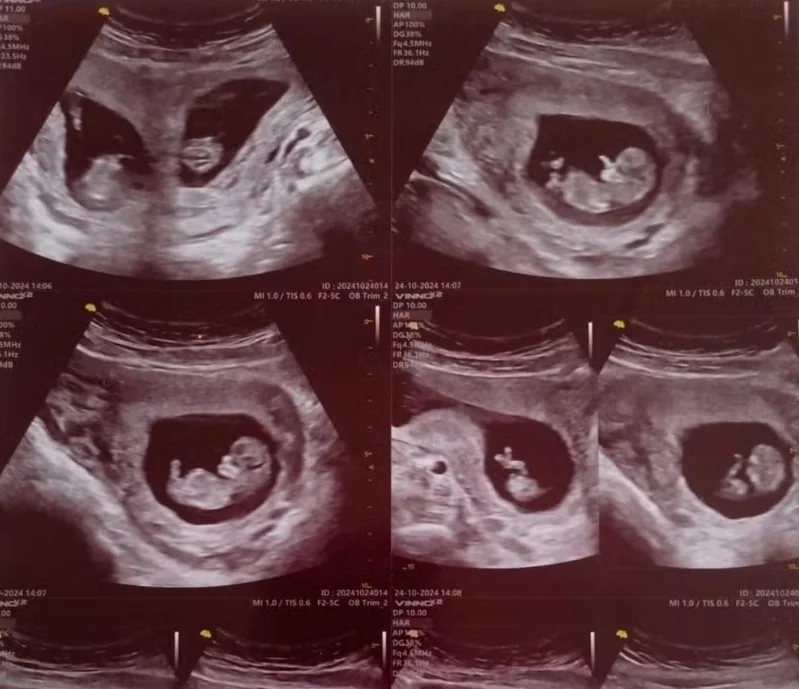

Focada na carreira como editora de laudos hospitalares, Paloma foi surpreendida novamente em setembro de 2024: estava grávida de gêmeos — um em cada útero, cada um com sua placenta e bolsa. “Levei um susto”, lembra. No primeiro ultrassom, apareceu apenas um bebê; uma semana depois, o exame revelou o segundo. O marido duvidou: achou que ela tinha editado a imagem.